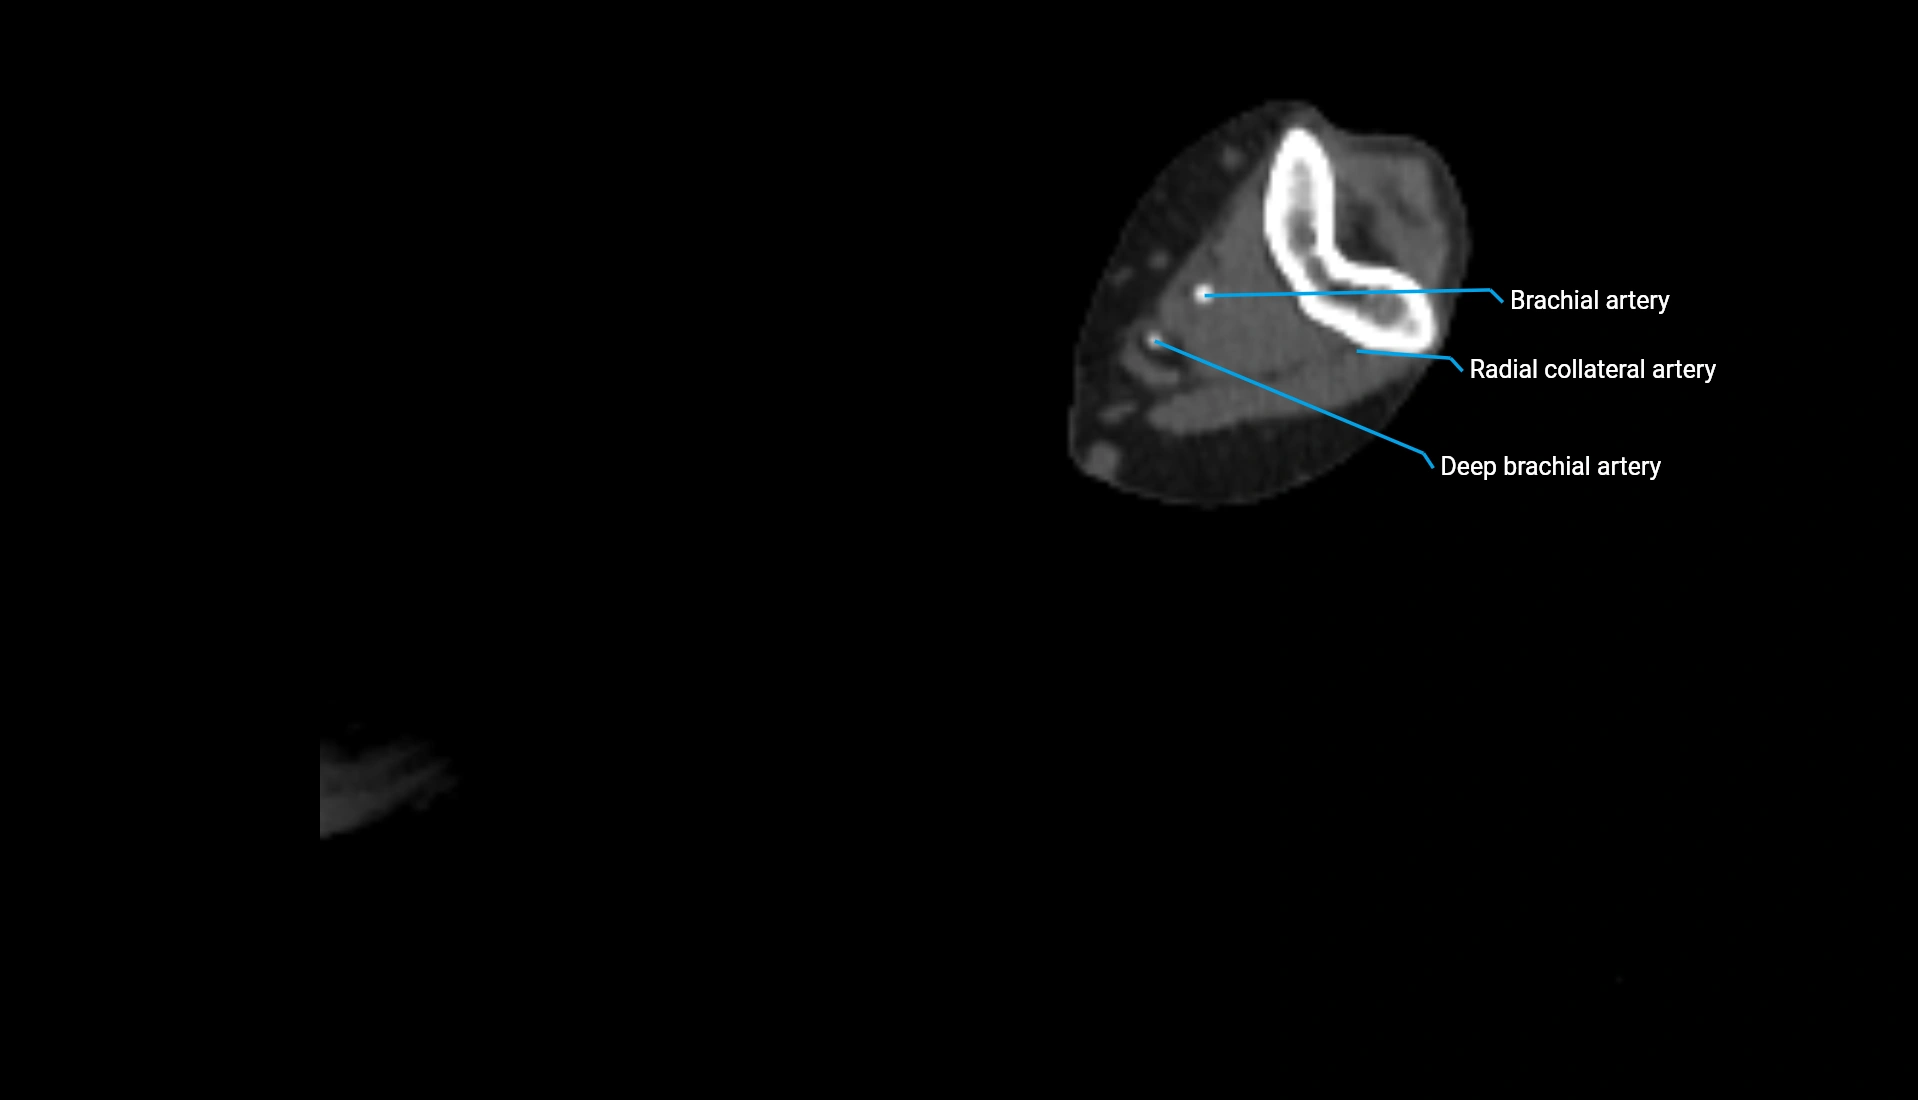

CT Appearance

Non-Contrast CT:

• Cortex: High-density, sharply defined

• Subchondral bone: Dense cancellous matrix

• Articular surface: Smooth concave contour articulating with the capitellum

• Excellent for evaluating bone integrity, alignment, and subtle fractures

Post-Contrast CT:

• Bone: No enhancement

• Joint capsule and synovium: Mild enhancement outlining the joint

• Improves contrast between soft tissues and bony margins

• Useful in detecting subtle joint abnormalities or postoperative changes